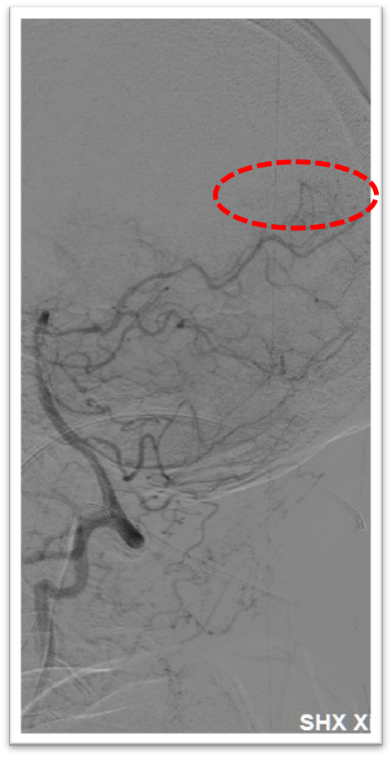

图4:DSA提示主动脉弓为牛角弓,左侧颈总动脉发自头臂干动脉,右侧颈内动脉造影提示前交通动脉开放,呈双干大脑前动脉,左侧大脑前动脉通过软膜支向左侧大脑中动脉供血区域代偿,双侧椎动脉均势供血,左侧大脑后动脉通过软膜支向前代偿供血;左侧颈总动脉闭塞,残端呈杯口状,近端可见白色血栓影,初步考虑栓塞性闭塞。